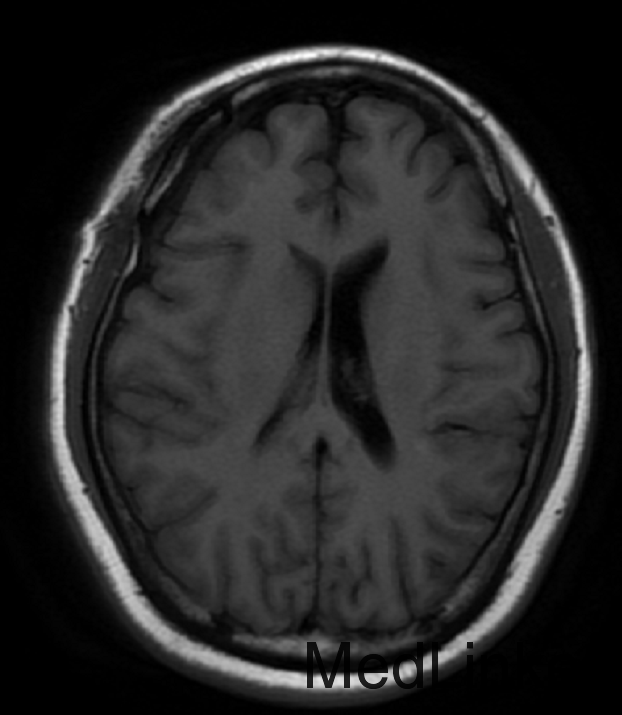

查体:双侧瞳孔等大等圆,直径约3mm,左侧对光反射灵敏,右侧对光反射迟钝,动眼自主,额纹对称,嘴角伸舌无歪斜。 2015-08-22当地医院查头颅MRI示:“右蝶骨嵴脑膜瘤”。

初步诊断:右]蝶骨嵴脑膜瘤。入院完善相关检查及术前准备,(2015-09-227日行磁共振(头部)检查提示:右侧蝶骨脊区占位,建议MRI增强。2015-09-29DSA示:右侧颈内动脉交通段、眼段狭窄,右侧前交通胚胎型,左侧椎动脉优势供血。垂体磁共振造影示:右侧蝶骨脊区占位,考虑脑膜瘤。排除手术禁忌症后于2015-09-29日行:开颅肿瘤切除术。